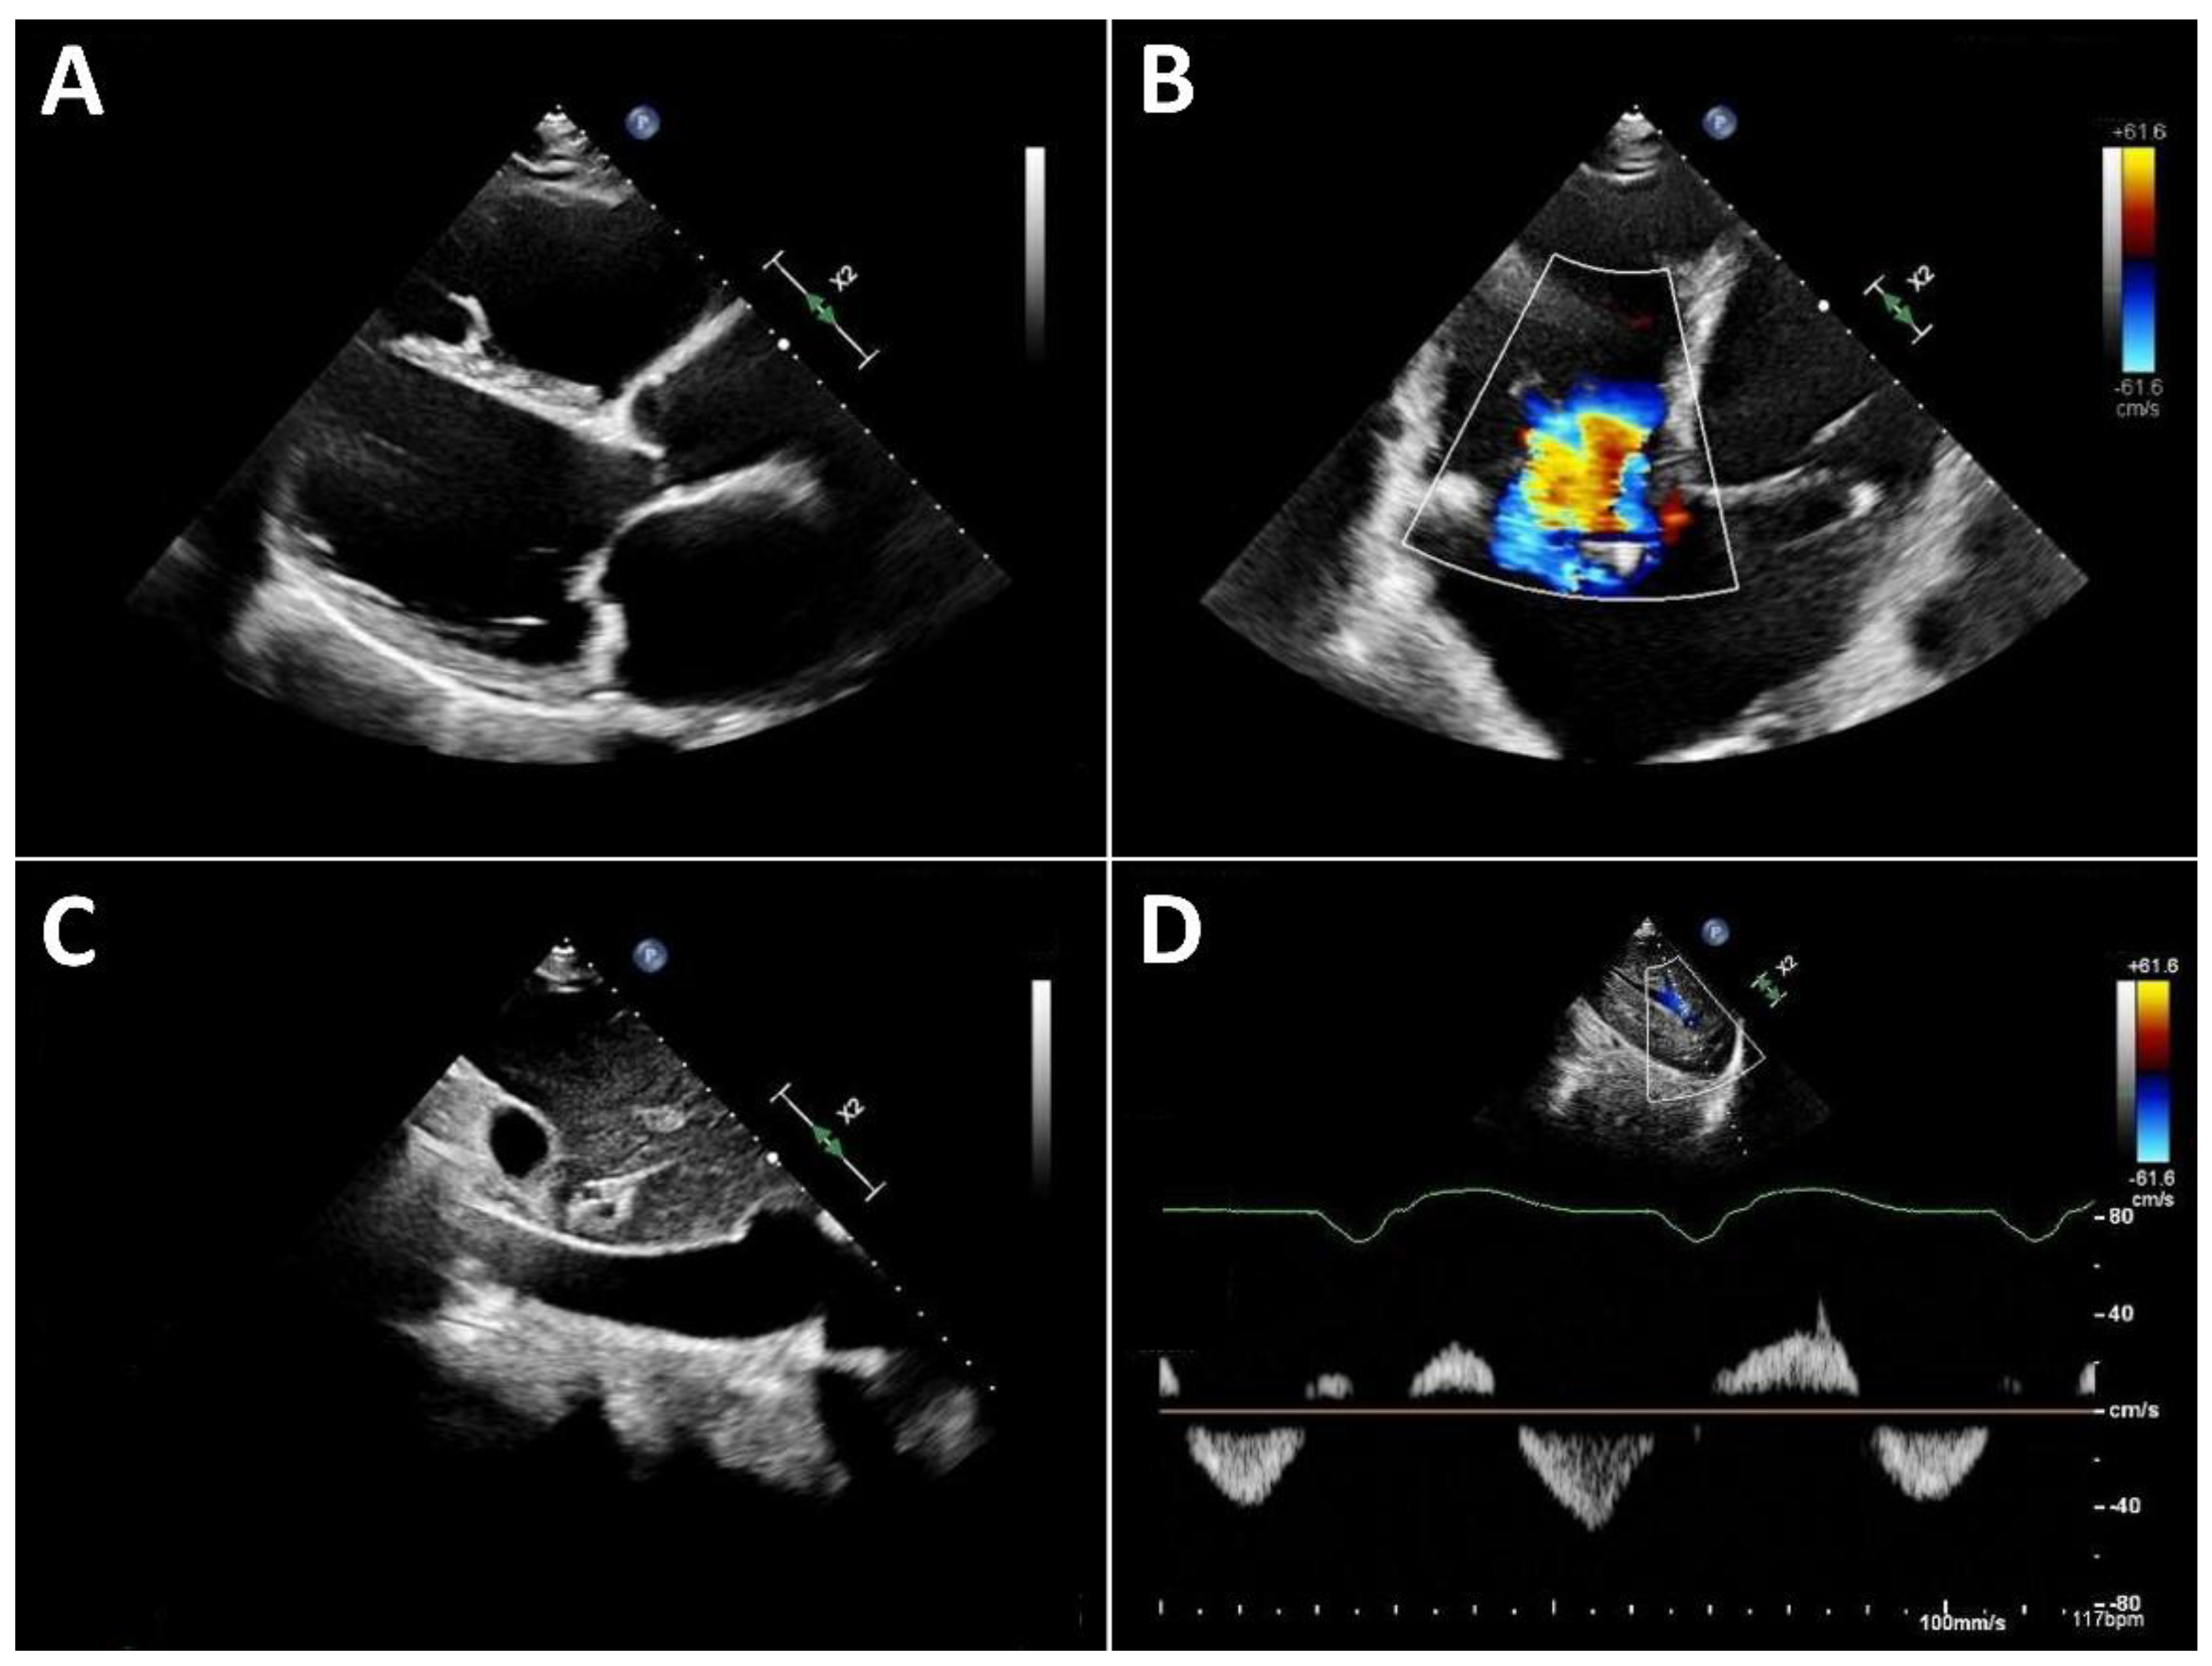

Typical echocardiographic signs of right ventricular failure include right ventricular dilatation, reflected by an increase in the proximal RV outflow tract (RVOT) diameter and RVD1 (Figure 3). This is frequently accompanied by dilatation of the tricuspid annulus with progressive tricuspid regurgitation. In severe cases, a leftward deviation of the interventricular septum may be observed. In advanced stages, the inferior vena cava is markedly dilated and exhibits significantly reduced respiratory variation. Quantification of tricuspid regurgitation can be performed using the standard guideline-recommended parameters, with a five-grade severity classification having proven useful [31].

Three-dimensional echocardiography of the right heart is often not feasible in many LVAD patients due to limited acoustic windows. Therefore, assessment of right ventricular (RV) function primarily relies on two-dimensional parameters. Longitudinal RV function is frequently reduced after cardiac surgery [32], a finding that is also observed in patients with LVAD support. Accordingly, tricuspid annular plane systolic excursion (TAPSE) typically decreases after LVAD implantation [7,33]. This reduction in longitudinal function is, however, partially compensated by an increase in radial RV contraction.

Consequently, right ventricular fractional area change (FAC) is recommended over TAPSE for the assessment of RV function in LVAD patients [34]. Importantly, RV function under LVAD support cannot be adequately characterized by a single parameter. Instead, it should always be interpreted in the context of preload (inferior vena cava filling), afterload (pulmonary artery pressure), septal position (reflecting adequate left ventricular filling), and the severity of tricuspid regurgitation.

Figure 3. Typical echocardiographic findings of severe right heart failure in a patient with LVAD support. A: Parasternal long-axis view showing a markedly dilated and hypokinetic proximal RVOT. B: Apical view demonstrating pronounced right ventricular dilatation and severe tricuspid regurgitation. C: Markedly dilated inferior vena cava with severely reduced respiratory variation. D: Systolic flow reversal in the hepatic veins.